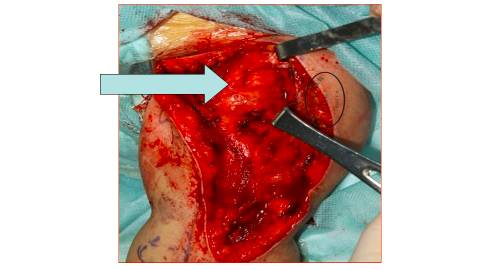

在这种情况下,我们设计一个游离腓骨。

首先我们探查肩关节的时候,可以看到肩袖的部分,还有三角肌的部分,它还是有一定功能。

因此我们设计的腓骨,就直接采用长段的骨缺损的恢复。利用长段的腓骨,来代替全长的肱骨。